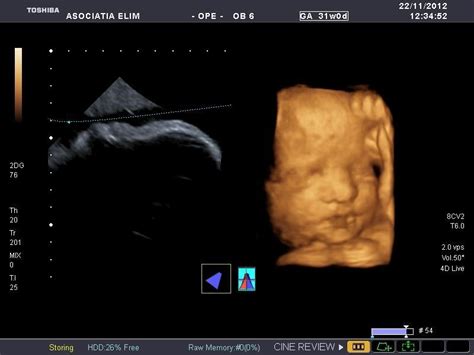

- Ultrasonografia: Efectuată între săptămânile 11-14 de sarcină.

- Ecografia țintită sau specializată: Indicată în caz de suspiciune a unei probleme de dezvoltare fetală.